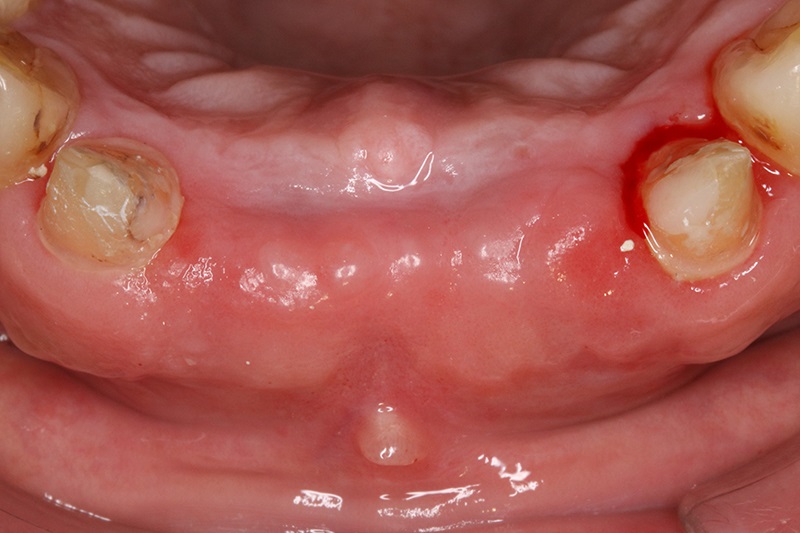

案例四

術前